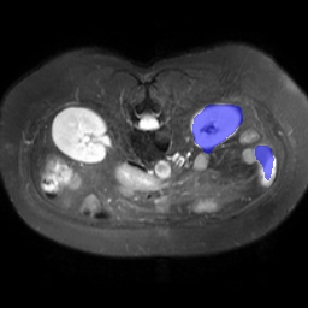

For CMR dataset, we only consider setting 1 because setting 2 is difficult to implement. The results are shown in Table 1 and Figure 4. In general, our proposed method is superior than others. For CHAOS dataset, we consider both setting 1 and setting 2. From the results, we can see the performance of our proposed model is higher than others on CHAOS and CMR datasets. Compared with Q-Net, our mean dice score on CHAOS dataset achieves about 82%. The segmentation results of the model are shown in Figure 5. In setting 2, the slices of the objects containing the test classes are all removed at training stage, and our model still performs well. As can be seen from the Table 2, the segmentation effect of the model on the right kidney is slightly worse than that of ALPNet, but overall, we achieve the best performance. The specific segmentation results are shown in Figure 6. As can be seen from the figure, other methods have excessive segmentation, but ours does not. Our segmentation results are more accurate and reduce redundant segmentation.